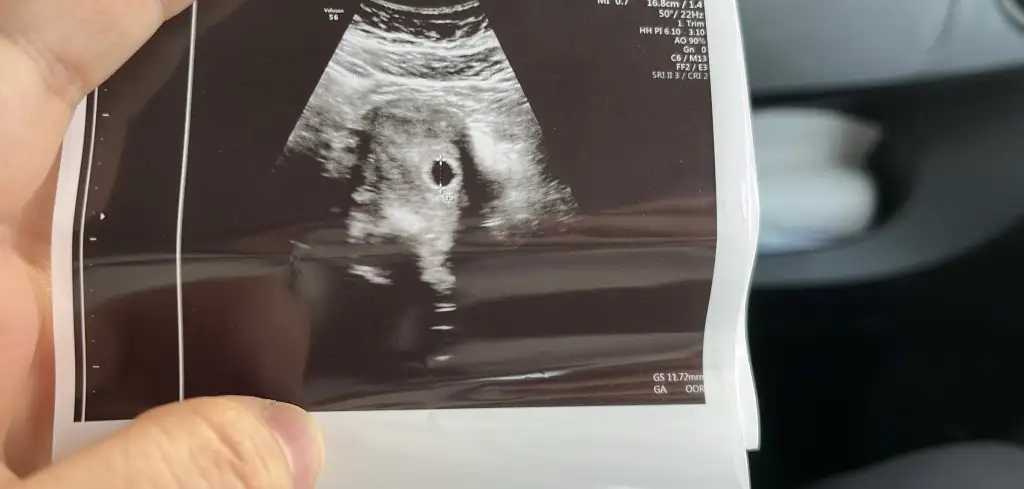

Kızlar biz keseyi gördükkkk 🙈 20 aralıkta transfer oldum çok minicik dedi doktor Yolk sac var dedi haftaya gidip kalp atışı dinlicez inşallah 🫠🌸🧿

7EF6ADBD-1BEB-423B-8C0F-2AA434AA5DD1.webp